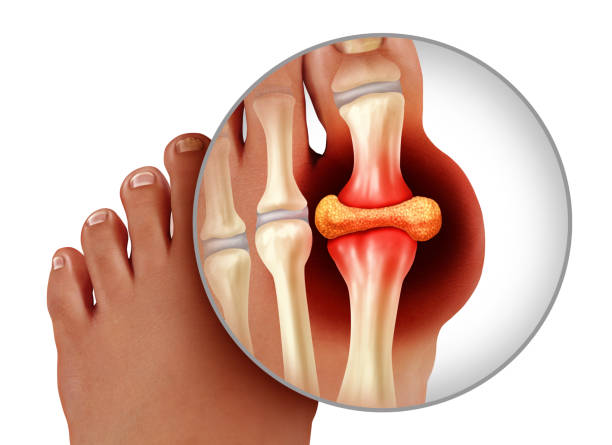

종자골염은 엄지발가락 아래쪽에 위치한 작은 뼈인 종자골(sesamoid bone)에 염증이나 통증이 발생하는 질환으로, 주로 반복적인 압력이나 충격으로 인해 발생합니다. 이 부위는 체중이 집중되는 부위 중 하나로, 보행이나 운동 시 지속적으로 자극을 받기 쉬우며, 특히 하이힐을 자주 신거나 달리기, 점프 등의 활동을 자주 하는 사람에게 잘 나타납니다. 종자골염은 초기에는 가벼운 통증으로 시작되지만, 시간이 지남에 따라 발바닥 앞쪽의 통증이 심해지고, 걸을 때 불편함을 초래하거나 발을 디딜 때 찌릿한 통증이 느껴지는 등 일상생활에 큰 영향을 미칠 수 있습니다. 본 글에서는 종자골염의 주요 원인 10가지를 중심으로, 나타나는 증상과 진단 방법, 그리고 효과적인 치료법과 재발 방지를 위한 관리법에 대해 구체적으로 살펴보겠습니다.

종자골염의 대표적인 증상은 발 앞쪽, 특히 엄지발가락 아래 부위의 통증입니다. 이 통증은 서 있거나 걷거나 뛸 때 더욱 심해지며, 장시간 활동 후에는 발바닥이 욱신거리거나 짓눌리는 느낌이 들 수 있습니다. 일부 환자는 국소적인 부기나 압통, 열감을 느끼기도 하며, 통증으로 인해 발을 절거나 무의식적으로 보행 자세가 바뀌는 경우도 있습니다. 증상이 심해지면 신발 신는 것조차 불편해지고, 심한 경우 발을 디디기 어려운 상태에 이를 수 있습니다. 특히 뻣뻣한 바닥을 맨발로 걸을 때 통증이 뚜렷해지며, 뼈를 누를 때 날카로운 통증이 느껴질 수 있습니다. 종자골염은 만성적으로 진행되는 경우가 많아 조기에 적절한 관리가 이루어지지 않으면 지속적인 통증과 활동 제한이 동반되며, 이로 인해 일상생활의 불편과 삶의 질 저하로 이어질 수 있습니다. 따라서 초기 증상을 인지하고 빠르게 대처하는 것이 매우 중요합니다.